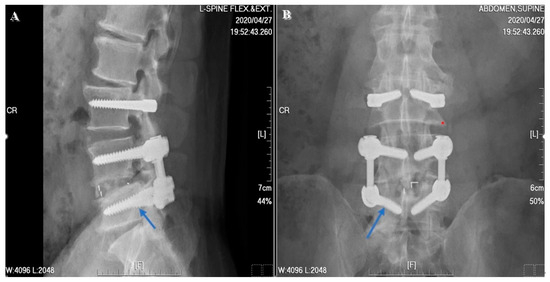

2.3. Surgical Techniques